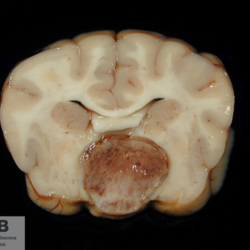

Pàgina anterior de 637 Pàgina següent 3181 total Canine Specie: Canine Organ: Nerve Lesion: - Lesion modifier: - Disease: - Files/Expedient: N-214/09 Not viewed Canine Specie: Canine Organ: Brain Lesion: Hemorrhage Lesion modifier: - Disease: - Files/Expedient: N-190/09 Not viewed Feline Specie: Feline Organ: Lung Lesion: Atelectasis Lesion modifier: - Disease: - Files/Expedient: N-167/09 Position: 136 (2 views) Canine Specie: Canine Organ: Pituitary gland Lesion: Carcinoma Lesion modifier: Carcinoma - Adenocarcinoma Disease: - Files/Expedient: N-113/09 Not viewed Canine Specie: Canine Organ: Pituitary gland Lesion: Carcinoma Lesion modifier: Carcinoma - Adenocarcinoma Disease: - Files/Expedient: N-113/09 Not viewed Pàgina anterior de 637 Pàgina següent Títol Select...Avian (Exotic) (110)Avian (Poultry) (76)Bovine (317)Canine (935)Caprine (47)Equine (257)Feline (326)Ferret (19)General (127)Marine mammal (22)Non-human primate (20)Ovine (328)Porcine (379)Rabbit (61)Reptile (38)Rodent (28)Wildlife (91) Format Select...- (60)Abomasum (37)Adrenal gland (10)Blood (7)Blood vessel (50)Body as a whole (19)Bone (57)Bone marrow (21)Brain (93)Cloaca (1)Diaphragm (2)Ear (5)Esophagus (39)Eye (16)Fetus (12)Gallbladder (23)Gizzard (2)Heart (265)Intestine (356)Joint (32)Kidney (443)Larynx (5)Liver (326)Lung (264)Lymph node (91)Mammary gland (10)Mediastinum (1)Muscle (22)Nasal cavity (22)Nerve (7)Omasum (5)Oral cavity (63)Ovary (14)Oviduct (8)Pancreas (7)Parathyroid (5)Penis (10)Peritoneum (65)Pharynx (9)Pituitary gland (6)Placenta (7)Prostate (8)Proventriculus (3)Reticulum (1)Rumen (28)Sinus (7)Skin (181)Spinal cord (15)Spleen (105)Stomach (125)Teeth (1)Testicle (11)Thoracic cavity (31)Thymus (13)Thyroid gland (5)Tongue (32)Tonsils (11)Trachea (11)Urethra (5)Urinay bladder (61)Uterus (27)Vagina (1)Vulva (1)Yolk sac (1) Cobertura Select...- (152)Abomasitis (26)Abscess (27)Acidosis (1)Adenocarcinoma (20)Adenoma (9)Aerosacculitis (6)Agenesis (1)Agnathia (1)Alopecia (7)Amyloidosis (12)Aneurysm (6)Angiectasis (1)Anthracosis (1)Arteritis (11)Arthritis (15)Arthrogryposis (6)Artifact (4)Ascites (13)Atelectasis (8)Atherosclerosis (5)Atresia (1)Atrial septal defect (2)Atrophy (10)Autolysis (7)Bronchitis (6)Bronchopneumonia (26)Cachexia (2)Carcinoma (103)Cardiomyopathy (19)Cellulitis (2)Chemodectoma (4)Cholangiohepatitis (4)Cholangitis (19)Cholecystitis (4)Cholestasis (5)Chondrodysplasia (2)Chondrosarcoma (2)Chronic passive congestion (13)Chylothorax (2)Cirrhosis (6)Coelomitis (3)Coenurus cerebralis (4)Colitis (40)Congestion (17)Conjunctivitis (5)Coronitis (3)Cryptorchidism (3)Cyst (25)Cystitis (24)Dermatitis (69)Diaphragmatic hernia (4)Dilation (28)Discospondylitis (1)Disseminated intravascular coagulation (7)Dyschondroplasia (1)Dysplasia (29)Ectopia cordis (1)Ectopic ureter (1)Edema (55)Emphysema (5)Encephalitis (5)Endocardiosis (14)Endocarditis (26)Endometritis (5)Enteritis (118)Enterolith (6)Epulis (3)Esophagitis (14)Fasciitis (1)Fibrosis (7)Fibrous osteodystrophy (8)Fistula (1)Folliculitis (3)Fracture (2)Gastritis (34)Gingivitis (5)Glioma (8)Glomerulonephritis (21)Glossitis (25)Glycogenosis (1)Gout (8)Granuloma (2)Granulosa cell tumor (4)Hemangioma (9)Hemangiosarcoma (46)Hematoma (8)Hemoglobinuria (2)Hemopericardium (12)Hemoperitoneum (2)Hemorrhage (100)Hemosiderosis (7)Hemothorax (2)Hepatitis (78)Hernia (11)Histiocytosis (3)Hydatid cyst (11)Hydrocephalus (9)Hydrometra (1)Hydronephrosis (22)Hydropericardium (6)Hydrothorax (3)Hydroureter (5)Hyperkeratosis (8)Hyperostosis (4)Hyperplasia (37)Hypertrophy (9)Hypopigmentation (1)Hypoplasia (7)Hypopyon (1)Impaction (6)Infarction (63)Insulinoma (6)Intussusception (5)Jaundice (17)Laminitis (2)Laryngitis (2)Leiomyoma (5)Leukemia (13)Lipidosis (36)Lipoma (7)Lymphadenitis (45)Lymphadenopathy (7)Lymphangiectasia (6)Lymphangitis (5)Lymphoma (221)Malacia (11)Malignant melanoma (15)Mast cell tumor (11)Mastitis (8)Megaesophagus (2)Melanosis (3)Melena (4)Meningioma (6)Meningitis (6)Meningocele (2)Meningoencephalitis (5)Mesothelioma (5)Methemoglobinemia (2)Mineralization (10)Mucocele (5)Mucometra (1)Multilobular bone tumor (1)Mummification (3)Myelofibrosis (1)Myocarditis (4)Myositis (5)Necrosis (81)Nephritis (113)Nephroblastoma (6)Nephrosclerosis (1)Nephrosis (14)Neuritis (1)Obstruction (13)Omasitis (4)Omphalitis (1)Omphalophlebitis (7)Orchitis (4)Osteoarthrosis (5)Osteomyelitis (9)Otitis (2)Palatoschisis (3)Pancreatitis (3)Panniculitis (3)Papilloma (7)Parakeratosis (14)Patent ductus arteriosus (6)Peliosis hepatis (1)Perforation (17)Pericarditis (35)Peritonitis (39)Persistent right aortic arch (1)Pharyngitis (2)Pheochromocytoma (2)Phlebitis (2)Placentitis (6)Pleuritis (21)Pleuropneumonia (24)Pneumonia (109)Pneumothorax (3)Polycystosis (14)Polyp (5)Polyserositis (6)Posthitis (1)Proctitis (4)Prolapse (3)Prostatitis (3)Proventriculitis (1)Pyelonephritis (24)Pyometra (6)Pyothorax (4)Rhinitis (11)Rumenitis (6)Rupture (24)Salpingitis (3)Sarcoma (57)Sclerosis (1)Scoliosis (2)Seminoma (2)Sequestrum (2)Serous atrophy (14)Sinusitis (7)Splenitis (14)Splenomegaly (9)Spondylitis (6)Spondylosis (1)Stenosis (9)Stomatitis (32)Tenosynovitis (2)Teratoma (3)Thricobezoar (2)Thrombosis (16)Tonsilitis (4)Torsion (13)Tracheitis (4)Tympany (7)Typhlitis (8)Typhlocolitis (4)Ulcer (43)Urethritis (1)Urolithiasis (36)Uroperitoneum (1)Uveitis (1)Vasculitis (15)Ventricular septal defect (3)Volvulus (11) Matèria Select... - (14)- (1653)- (152)Abomasitis - Catarrhal (2)Abomasitis - Catarrhal-hemorrhagic (1)Abomasitis - Chronic (1)Abomasitis - Fibrinous-necrotizing (2)Abomasitis - Hyperplasic (5)Abomasitis - Hyperplasic - Chronic (1)Abomasitis - Necrotic (1)Abomasitis - Necrotizing (2)Abomasitis - Ulcerative (5)Adenocarcinoma (9)Aerosacculitis - Granulomatous (1)Amyloidosis - Chronic (1)Arteritis - Necrotic (2)Arteritis - Necrotizing (1)Arthritis - Chronic (4)Arthritis - Fibrinous-purulent (3)Arthritis - Serous (4)Arthritis - Subacute (1)Ascites - Serous (1)Atrophy - Serous (1)Bronchitis - Catarrhal (3)Bronchitis - Suppurative (1)Bronchopneumonia - Catarrhal-purulent (17)Bronchopneumonia - Fibrinous (1)Bronchopneumonia - Granulomatous (1)Bronchopneumonia - Purulent (1)Bronchopneumonia - Suppurative (5)Carcinoma - Adenocarcinoma (33)Carcinoma - Adenocarcinoma - Hepatocellular (2)Carcinoma - Adenocarcinoma - Mucinous (1)Carcinoma - Basosquamous (1)Carcinoma - Cholangiocellular (3)Carcinoma - Hepatocellular (4)Carcinoma - Metastatic (3)Carcinoma - Squamous cell carcinoma (13)Carcinoma - Transitional cell (2)Cardiomyopathy - Dilated (13)Cardiomyopathy - Hypertrophic (6)Cellulitis - Necrotizing (1)Cholangitis - Chronic (8)Cholangitis - Hyperplasic (3)Cholecystitis - Fibrinous-necrotizing (1)Coelomitis - Fibrinous (1)Coelomitis - Granulomatous (1)Colitis - Catarrhal (3)Colitis - Catarrhal-hemorrhagic (1)Colitis - Fibrinous (1)Colitis - Fibrinous-necrotizing (1)Colitis - Fibrinous-necrotizing (Diphtheritic) (6)Colitis - Granulomatous (2)Colitis - Hemorrhagic (4)Colitis - Hemorrhagic-necrotizing (3)Colitis - Necrotizing (2)Colitis - Ulcerative (6)Congestion - Chronic (2)Conjunctivitis - Hyperplasic (1)Conjunctivitis - Purulent (3)Coronitis - Ulcerative (1)Cystitis - Chronic (3)Cystitis - Fibrinous (1)Cystitis - Fibrinous-necrotizing (1)Cystitis - Follicular (1)Cystitis - Hemorrhagic (6)Cystitis - Hemorrhagic-ulcerative (1)Cystitis - Necrotizing (9)Cystitis - Perforated (1)Dermatitis - Granulomatous (14)Dermatitis - Hyperkeratotic (10)Dermatitis - Hyperplasic (proliferative) (1)Dermatitis - Hyperplastic (10)Dermatitis - Necrotizing (4)Dermatitis - Pustular (4)Dermatitis - Ulcerative (2)Dilation - Chronic (1)Discospondylitis - Necrotizing (1)Dysplasia - Follicular (5)Edema - Interstitial (6)Emphysema - Interstitial (1)Encephalitis - Granulomatous (1)Encephalitis - Nonsuppurative (1)Endocardiosis - Mitral (7)Endocardiosis - Mitral - Chronic (5)Endocarditis - Valvular (6)Endocarditis - Valvular - Mitral (7)Endocarditis - Valvular - Pulmonic (1)Endocarditis - Valvular - Subacute (1)Endocarditis - Valvular - Subaortic (5)Endocarditis - Valvular - Tricuspid (4)Endometritis - Purulent (3)Endometritis - Purulent-hemorrhagic (2)Enteritis - Catarrhal (23)Enteritis - Catarrhal - Acute (1)Enteritis - Catarrhal-hemorrhagic (5)Enteritis - Catarrhal-hemorrhagic - Acute (2)Enteritis - Fibrinous (16)Enteritis - Fibrinous - Acute (3)Enteritis - Fibrinous-necrotizing (7)Enteritis - Granulomatous (14)Enteritis - Granulomatous - Chronic (1)Enteritis - Granulomatous - Multifocal (1)Enteritis - Hemorrhagic (17)Enteritis - Hemorrhagic - Acute (1)Enteritis - Hemorrhagic-necrotizing (1)Enteritis - Hyperplasic (proliferative) (4)Enteritis - Necrotizing (4)Enteritis - Necrotizing - Acute (1)Enteritis - Necrotizing - Hemorrhagic (1)Enteritis - Necrotizing-ulcerative (2)Enteritis - Ulcerative (1)Enteritis - Ulcerative-hemorrhagic (1)Esophagitis - Erosive-ulcerative (6)Esophagitis - Necrotizing (4)Esophagitis - Ulcerative (1)Esophagitis - Ulcerative-necrotizing (1)Fasciitis - Fibrinous-purulent (1)Folliculitis - Purulent (2)Gastritis - Catarrhal (2)Gastritis - Chronic (1)Gastritis - Follicular (1)Gastritis - Hemorrhagic (2)Gastritis - Hemorrhagic-necrotizing (1)Gastritis - Hypertrophic (2)Gastritis - Inclusion bodies (1)Gastritis - Mineralization (1)Gastritis - Mycotic (1)Gastritis - Necrotizing (2)Gastritis - Ulcerative (6)Gastritis - Uremic (3)Gingivitis - Erosive (2)Gingivitis - Hyperplasic (proliferative) (1)Gingivitis - Necrotizing (1)Glomerulonephritis - Chronic (7)Glomerulonephritis - Membranoproliferative (3)Glomerulonephritis - Membranoproliferative - Chronic (1)Glomerulonephritis - Membranous (3)Glomerulonephritis - Membranous - Chronic (1)Glomerulonephritis - Proliferative (2)Glomerulonephritis - Subacute (1)Glossitis - Erosive (2)Glossitis - Granulomatous (6)Glossitis - Hyperplasic (1)Glossitis - Hyperplasic (proliferative) (2)Glossitis - Hyperplastic (1)Glossitis - Necrotizing (2)Glossitis - Necrotizing - Focal (1)Glossitis - Ulcerative (6)Glossitis - Ulcerative - Multifocal (1)Glossitis - Ulcerative - Subacute (1)Glycogenosis (1)Granuloma - Eosinophilic (1)Hemangiosarcoma - Metastatic (2)Hemorrhage - Acute (1)Hemorrhage - Subcapsular (3)Hepatitis - Abscess (9)Hepatitis - Acute (3)Hepatitis - Chronic (4)Hepatitis - Chronic interstitial (6)Hepatitis - Granulomatous (7)Hepatitis - Interstitial - Multifocal (1)Hepatitis - Interstitial - Subacute (1)Hepatitis - Necrotizing (17)Hepatitis - Necrotizing - Acute (2)Hepatitis - Necrotizing - Hemorrhagic (1)Hepatitis - Necrotizing - Subacute (1)Hepatitis - Pyogranulomatous (7)Hepatitis - Subacute (4)Hydronephrosis - Chronic (1)Hydropericardium - Chronic (1)Hyperplasia - Erythroid (1)Hyperplasia - Lymphoid (3)Hyperplasia - Myeloid (1)Hyperplasia - Nodular (8)Hypertrophy - Concentric (2)Hypertrophy - Eccentric (3)Infarction - Acute (17)Infarction - Acute - Multifocal (2)Infarction - Chronic (5)Infarction - Chronic - Multifocal (1)Infarction - Subacute (18)Infarction - Subacute - Focal (2)Laminitis - Chronic (2)Laryngitis - Necrotic (1)Laryngitis - Necrotizing (1)Leukemia - Lymphoid leukemia (2)Leukemia - Non-lymphoid leukemia (6)Lipidosis - Multifocal (1)Lipidosis - Panlobular (1)Lipidosis - Panlobular - Generalized (2)Lymphadenitis - Granulomatous (24)Lymphadenitis - Granulomatous - Chronic (3)Lymphadenitis - Hemorrhagic (1)Lymphadenitis - Necrotizing (5)Lymphadenitis - Necrotizing (caseous) (11)Lymphangitis - Granulomatous (1)Lymphangitis - Purulent (1)Lymphangitis - Ulcerative (1)Lymphoma - Alimentary lymphoma (7)Lymphoma - Cutaneous lymphoma (6)Lymphoma - Lymphosarcoma (2)Lymphoma - Mediastinal lymphoma (1)Lymphoma - Multicentric lymphoma (29)Malignant melanoma - Malignant (1)Malignant melanoma - Metastatic (1)Mast cell tumor - Metastatic (1)Mastitis - Fibrinous-purulent (2)Mastitis - Necrotic (1)Mastitis - Purulent (3)Mastitis - Suppurative (1)Meningitis - Fibrinous-purulent (2)Meningitis - Purulent (4)Meningoencephalitis - Necrotizing (3)Meningoencephalitis - Nonsuppurative (2)Mineralization - Metastatic (4)Myocarditis - Fibrous - Chronic (1)Myocarditis - Granulomatous (1)Myositis - Purulent (2)Necrosis - Acute (1)Necrosis - Cortical (5)Necrosis - Follicular (1)Necrosis - Papillary (8)Necrosis - Papillary - Acute (3)Necrosis - Subacute (3)Necrosis - Tubular (6)Nephritis - Embolic (2)Nephritis - Embolic suppurative (7)Nephritis - Granulomatous (27)Nephritis - Granulomatous - Chronic (1)Nephritis - Granulomatous - Multifocal (1)Nephritis - Interstitial (6)Nephritis - Interstitial - Acute (4)Nephritis - Interstitial - Chronic (41)Nephritis - Interstitial - Subacute (12)Nephritis - Purulent (7)Nephritis - Purulent - Acute (2)Nephritis - Purulent - Multifocal (3)Nephrosis - Cholemic (3)Nephrosis - Hemoglobinuric (10)Omasitis - Fibrinous-necrotizing (1)Omasitis - Hyperkeratotic (1)Omasitis - Necrotizing (2)Omphalophlebitis - Fibrinous-purulent (2)Omphalophlebitis - Purulent (3)Orchitis - Necrotizing (1)Osteomyelitis - Necrotizing (7)Osteomyelitis - Purulent (2)Otitis - Necrotizing (1)Otitis - Proliferative (1)Pancreatitis - Acute (1)Pancreatitis - Chronic (1)Pancreatitis - Granulomatous (1)Panniculitis - Fibrinous-purulent (1)Panniculitis - Necrotic (1)Panniculitis - Parasitic (1)Perforation - Acute (2)Pericarditis - Fibrinous (19)Pericarditis - Fibrinous - Subacute (1)Pericarditis - Fibrinous-necrotizing (1)Pericarditis - Fibrinous-purulent (3)Pericarditis - Fibrous (1)Pericarditis - Fibrous - Chronic (1)Pericarditis - Gangrenous (6)Pericarditis - Granulomatous (1)Pericarditis - Granulomatous - Chronic (2)Peritonitis - Acute (1)Peritonitis - Fibrinous (11)Peritonitis - Fibrinous - Subacute (1)Peritonitis - Fibrinous-purulent (5)Peritonitis - Fibrous (3)Peritonitis - Granulomatous (6)Peritonitis - Purulent (1)Peritonitis - Purulent-hemorrhagic (1)Peritonitis - Pyogranulomatous (3)Pharyngitis - Fibrinous-necrotizing (1)Pharyngitis - Ulcerative (1)Pheochromocytoma - Metastatic (1)Phlebitis - Purulent (1)Placentitis - Fibrinous-necrotizing (1)Placentitis - Necrotic (1)Placentitis - Necrotizing (1)Pleuritis - Chronic (1)Pleuritis - Fibrinous (3)Pleuritis - Fibrinous-purulent (2)Pleuritis - Fibrous (2)Pleuritis - Granulomatous (3)Pleuritis - Hyperplastic (2)Pleuritis - Purulent (2)Pleuritis - Pyogranulomatous (1)Pleuropneumonia - Fibrinous (13)Pleuropneumonia - Fibrinous-necrotizing (5)Pleuropneumonia - Granulomatous (2)Pleuropneumonia - Hemorrhagic-necrotizing (4)Pneumonia - Aspiration (11)Pneumonia - Bronchointerstitial (4)Pneumonia - Bronchointerstitial - Subacute (1)Pneumonia - Embolic (5)Pneumonia - Granulomatous (37)Pneumonia - Granulomatous - Multifocal (4)Pneumonia - Hemorrhagic-necrotizing (2)Pneumonia - Interstitial (7)Pneumonia - Interstitial - Acute (8)Pneumonia - Interstitial - Chronic (6)Pneumonia - Interstitial - Subacute (15)Pneumonia - Necrotizing (2)Pneumonia - Pyogranulomatous (2)Pneumonia - Verminous (5)Polyserositis - Fibrinous (6)Polyserositis - Fibrous (1)Proctitis - Fibrinous-necrotizing (1)Proctitis - Parasitic (2)Prostatitis - Purulent (1)Pyelonephritis - Acute (2)Pyelonephritis - Chronic (3)Rhinitis - Catarrhal (2)Rhinitis - Fibrinous (1)Rhinitis - Granulomatous (4)Rhinitis - Purulent (3)Rumenitis - Acute (1)Rumenitis - Erosive (1)Rumenitis - Necrotizing (1)Rupture - Acute (3)Sarcoma - Fibrosarcoma (12)Sarcoma - Hemangiosarcoma (11)Sarcoma - Histiocytic (7)Sarcoma - Metastatic (1)Sarcoma - Multilobular tumor of bone (1)Sequestrum - Chronic (2)Sinusitis - Suppurative (1)Splenitis - Granulomatous (8)Splenitis - Granulomatous - Chronic (1)Splenitis - Necrotizing (3)Splenitis - Necrotizing (caseous) (2)Spondylitis - Necrotizing (2)Stenosis - Intestinal (1)Stenosis - Valvular - Subaortic (4)Stomatitis - Erosive (12)Stomatitis - Erosive-ulcerative (3)Stomatitis - Fibrinous-necrotizing (1)Stomatitis - Fibrinous-necrotizing (Diphtheritic) (1)Stomatitis - Granulomatous (1)Stomatitis - Hyperplasic (1)Stomatitis - Hyperplasic (proliferative) (1)Stomatitis - Necrotizing (2)Stomatitis - Ulcerative (5)Stomatitis - Ulcerative - Multifocal (1)Stomatitis - Ulcerative-necrotizing (1)Tonsilitis - Necrotizing (4)Torsion - Acute passive hyperemia (5)Tracheitis - Catarrhal (3)Tracheitis - Fibrinous (1)Tracheitis - Granulomatous (1)Typhlitis - Catarrhal (1)Typhlitis - Fibrinous-necrotizing (2)Typhlitis - Hemorrhagic (2)Typhlitis - Ulcerative-hemorrhagic (1)Typhlocolitis - Fibrinous-necrotizing (2)Typhlocolitis - Proliferative (1)Ulcer - Chronic (6)Ulcer - Multifocal (2)Ulcer - Mycotic (1)Ulcer - Perforated (6)Urethritis - Hemorrhagic (1)Urolithiasis - Chronic (2)Uveitis - Granulomatous (1)Vasculitis - Granulomatous (1)Vasculitis - Necrotizing (1) Editor Select...- (1970)Acidosis (2)Actinobacillosis (Pleuropneumonia) (11)Aelurostrongylosis (2)African horse sickness (13)African swine fever (14)Alopecia X (1)Anaplasmosis (4)Anthrax (2)Aortic thromboembolism (feline) (7)Ascariasis (15)Aspergillosis (18)Atopic dermatitis (1)Atrophic rhinitis (3)Babesiosis (6)Blackhead (1)Bluetongue (11)Border disease (2)Bovine viral diarrhea (21)Brucellosis (2)Candidiasis (5)Canine distemper (14)Caprine arthritis-encephalitis (2)Capture myopathy (1)Cardiac insufficiency (17)Caseous lymphadenitis (7)Chlamydiosis (2)Classical swine fever (19)Clostridiosis (19)Coccidiosis (9)Coenurosis (4)Colibacillosis (21)Contagious ecthyma (7)Copper toxicosis (11)Cowdriosis (Heartwater) (3)Cryptococcosis (3)Cryptosporidiosis (2)Cysticercosis (23)Demodicosis (1)Diabetes (1)Dicrocoeliosis (5)Dictyocaulosis (4)Dirofilariasis (7)Discoid lupus erythematosus (3)Echinococcosis (17)Edema disease (7)Egg drop syndrome (1)Encephalitozoonosis (5)Enterotoxemia (1)Enzootic bovine leukosis (46)Epitheliogenesis imperfecta (3)Equine rhinopneumonitis (2)Equine verminous arteritis (strongylosis) (7)Erysipelas (5)Exudative epidermitis (7)Fasciolasis (11)Feline eosinophilic dermatoses (1)Feline hepatic lipidosis (8)Feline histiocytosis (4)Feline infectious peritonitis (38)Feline leukemia (4)Feline lower urinary tract disease (3)Feline panleukopenia (16)Feline viral rhinotracheitis (1)Flea allergy dermatitis (1)Foot and mouth disease (2)Gasterophilosis (4)Glasser's disease (15)Gousiekte (4)Gout (6)Haemonchosis (9)Hemolytic anemia (4)Hemorrhagic diathesis (1)Hepatic insufficiency (11)Hepatosis dietetica (7)Herpesvirosis (6)Hyperadrenocorticism (7)Hyperparathyroidism (10)Hypertrophic osteopathy (6)Hypervitaminosis D (1)Hypodermosis (1)Inclusion body hepatitis (4)Infectious bovine rhinotracheitis (5)Infectious bronchitis (5)Infectious canine hepatitis (13)Influenza (4)Juvenile nephropathy (8)Lamb dysentery (4)Leishmaniasis (28)Leptospirosis (1)Leukosis (5)Listeriosis (4)Lumpy skin disease (3)Maedi-visna (4)Malignant catarrhal fever (12)Mange (6)Mannheimiosis (5)Marek's disease (7)Metabolic bone disease (2)Mucoid enteropathy (5)Mulberry heart disease (5)Myasis (1)Mycobacteriosis (22)Mycosis fungoides (6)Myxomatosis (3)Necrobacillosis (5)Neonatal isoerythrolysis (6)Nocardiosis (4)Oestrosis (2)Onchocerciasis (1)Osteochondrosis (1)Ostertagiosis (6)Ovine pulmonary adenocarcinoma (5)Oxyuriasis (1)Pacheco's disease (4)Papillomatosis (6)Paratuberculosis (18)Parvovirosis (17)Pasteurellosis (11)Pemphigus foliaceus (1)Periodontal disease (1)Polioencephalomalacia of ruminants (4)Polyarteritis nodosa (3)Polycystic kidney disease (13)Porcine circovirosis (11)Porcine dermatitis and nephropathy syndrome (9)Porcine proliferative enteropathy (4)Porcine reproductive and respiratory syndrome (6)Porcine stress syndrome (1)Pox (13)Pregnancy toxemia (3)Proventricular dilatation disease (2)Pseudotuberculosis (yersiniosis) (2)Psittacine beak and feather disease (PBFD) (5)Pyoderma (4)Q fever (4)Rabbit hemorrhagic disease (2)Renal insufficiency (12)Reticuloendotheliosis (2)Rhodococcosis (1)Rickets (1)Rinderpest (2)Salmonellosis (34)Sarcosporidiosis (2)Schmallenberg (7)Septicemia (23)Spirocercosis (11)Streptococcosis (5)Strongylosis (1)Swine dysentery (5)Systemic coronavirosis (5)Tetralogy of Fallot (5)Theileriosis (13)Thromboembolism (5)Toxoplasmosis (11)Transmissible viral proventriculitis (1)Traumatic reticuloperitonitis (3)Traumatism (16)Tuberculosis (58)Ulcerative lymphangitis (1)Uremic syndrome (20)Viral arthritis (6)White muscle disease (9)Wobbler syndrome (2)Xanthomatosis (1)Zygomycosis (4) Idioma Select...- (1180)Bacterial (501)Degeneration (106)Fungal (46)Hemodynamic (112)Idiopathic (22)Inflammation (58)Malformation (88)Neoplasia (343)Nutritional (41)Parasitic (243)Physical/Chemical (93)Toxic (44)Viral (304) Ítem destacat Avian (Poultry) Broilers. Livers are swollen, pale, friable with petechial or echymotic hemorrhages. Adenovirus (group I).